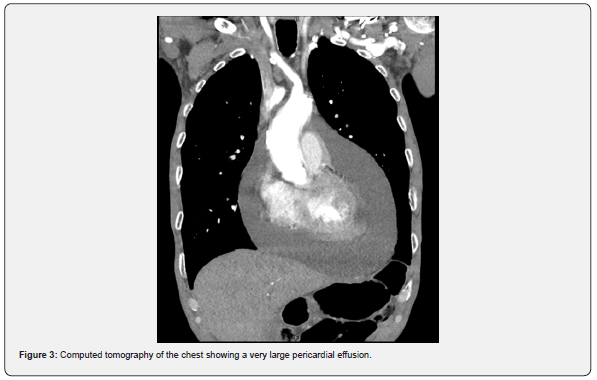

A computed tomography of the chest with contrast (Figure 3) showed a large pericardial effusion and abnormal irregular nodule in the right lung apex with para-tracheal, hilar, and abnormal appearing right supraclavicular lymph node indicative of lung cancer. Further workup with positron emission tomography and computed tomography of the chest showed findings consistent with lung malignancy. MRI of the brain did not reveal any metastasis though detected extensive microvascular changes with numerous lacunar infarcts. Two days after the initial pericardiocentesis, repeat echocardiogram revealed a re-accumulation of the pericardial effusion circumferentially without evidence of increased intra-pericardial pressures.